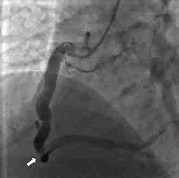

例1,男,47岁,以阵发性心前区疼痛半月入院。大量吸烟史25年,高血压病史5年。查体:心率85次/分,血压150/90mmHg,心尖区可闻及Ⅱ级收缩期杂音。血CHOL5.25mmol/L,TG3.36mmol/L。心脏彩超:左心房内径40mm,左心室舒张末期内径55mm,下壁节段性运动减弱。心电图:Ⅱ、Ⅲ、aVF导联可见病理性Q波,T波倒置。入院后行冠状动脉造影示:三支冠状动脉严重扩张;左前降支(LAD)左回旋支(LCX)前向血流TIMIⅢ级(图1);右冠状动脉(RCA)血流TIMIⅡ级,第二段与第三段反折处可见血栓影(图2)。行冠状动脉内超声(IVUS)示: 三支冠状动脉显著扩张,未见明显动脉粥样硬化斑块,RCA第二段与第三段反折处可见血栓。给予抗凝、抗血小板、转换酶抑制剂、他汀类降脂药物及硝酸酯类药物治疗,患者胸痛症状消失。随访半年,无胸痛症状发生。

图2:例1冠状动脉造影显示右冠状动脉显著扩张,第二段与第三段反折处可见血栓影(箭头指示)